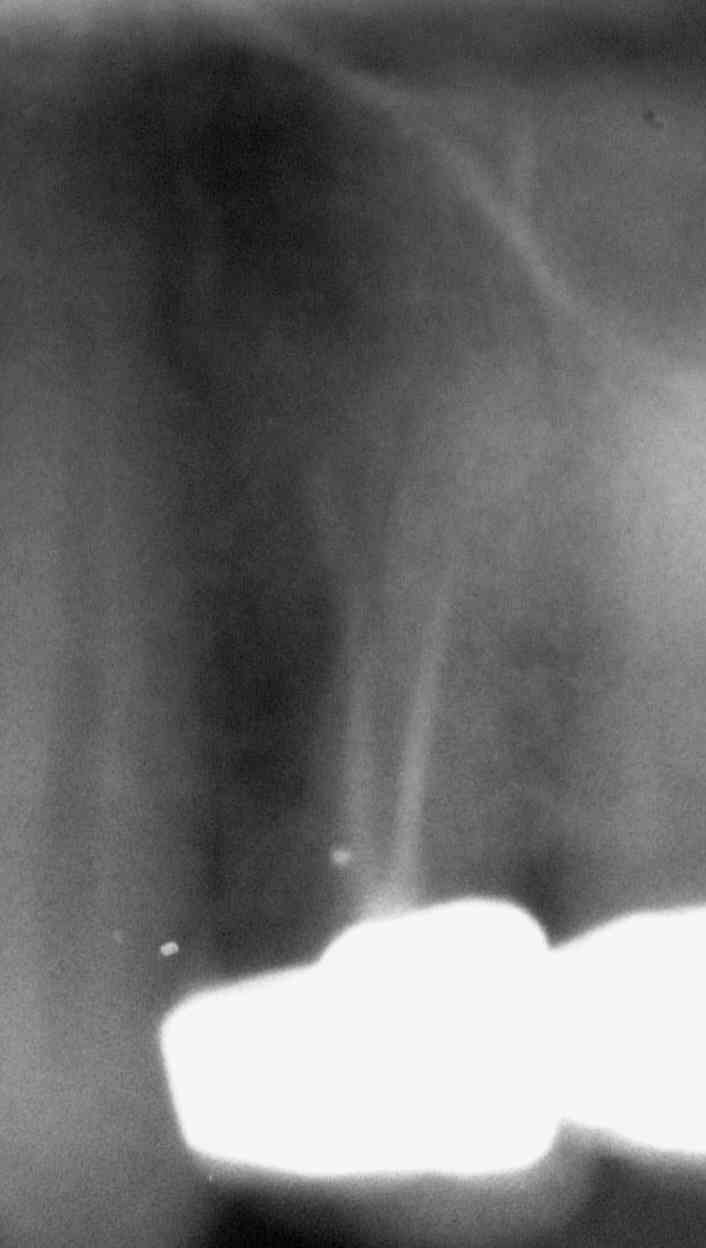

Die diffuse apikale Aufhellung über dem Zahn 24 mit insuffizienter WF war bereits auf dem OPT anlässlich der Erstuntersuchung  im November 1989 deutlich erkennbar (Klick!)

Das Auffinden der Kanäle nach kompletter Kronenfraktur im November 1998 war nicht sehr problematisch (Klick!)

Beim Abfüllen im Dezember 1998  kam es zu einer Überpressung in einen zystischen Hohlraum innerhalb der diffusen Aufhellung oberhalb der mesialen Wurzel. Stiftaufbau mit 2 Radix-Ankern und Kronenaufbau mit Kunststoff in SÄT (Klick!)

Verlaufskontrolle im September 2006. Der überpresste Sealer wird unter röntgenologisch knochendichter Ausheilung nur sehr langsam resorbiert, was nach unserer Erfahrung dafür spricht, dass eine Zyste abgefüllt wurde (Klick!)